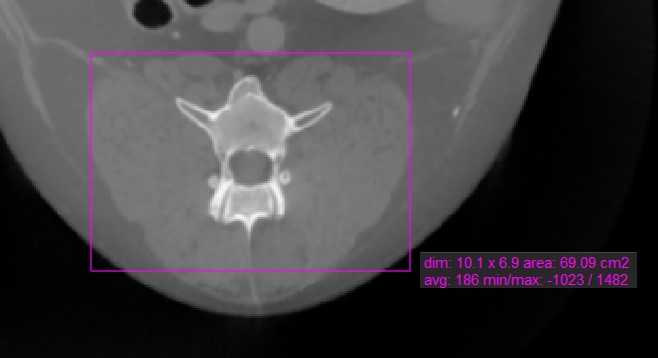

Rectangle

../_images/image96.jpg

The Rectangle tool offers users the ability to mark a rectangular area on the active image slice.

Select the Rectangle tool and assign it to one of the available mouse buttons. Start the measurement by pressing on the active image slice and drag the mouse to obtain a rectangular shape. Release the mouse when satisfied with the size of the marked area.

All available measurement values are displayed alongside the measurement.

Modify the marked area by moving one of the four points of the rectangular shape using the Default tool.

../_images/image204.jpg